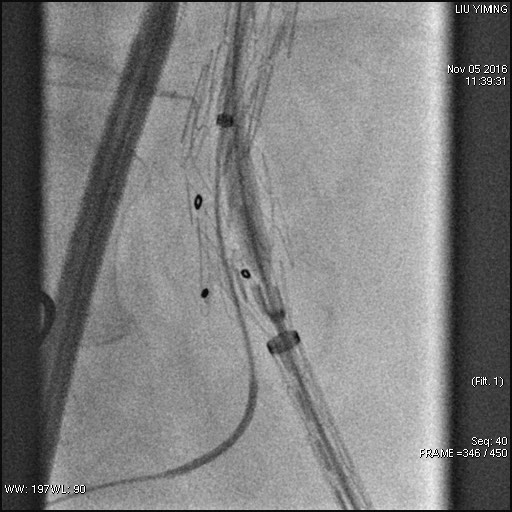

其中,在复杂主动脉病变腔内修复术应用手术直播中,郭伟教授带领其团队使用先健科技公司的髂动脉分叉支架系统(IBD)以完全腔内重建的方式成功修复复杂腹主动脉瘤及髂动脉瘤。该例手术患者为64岁的男性,被诊断为肾下腹主动脉瘤,瘤体最大直径约6.5cm,双侧髂动脉瘤。患者成功植入先健科技IBD支架,定位准确,无内漏,成功保留了左侧髂内动脉,术后造影显示髂内动脉通畅。

图:术前造影、术中造影、术后造影